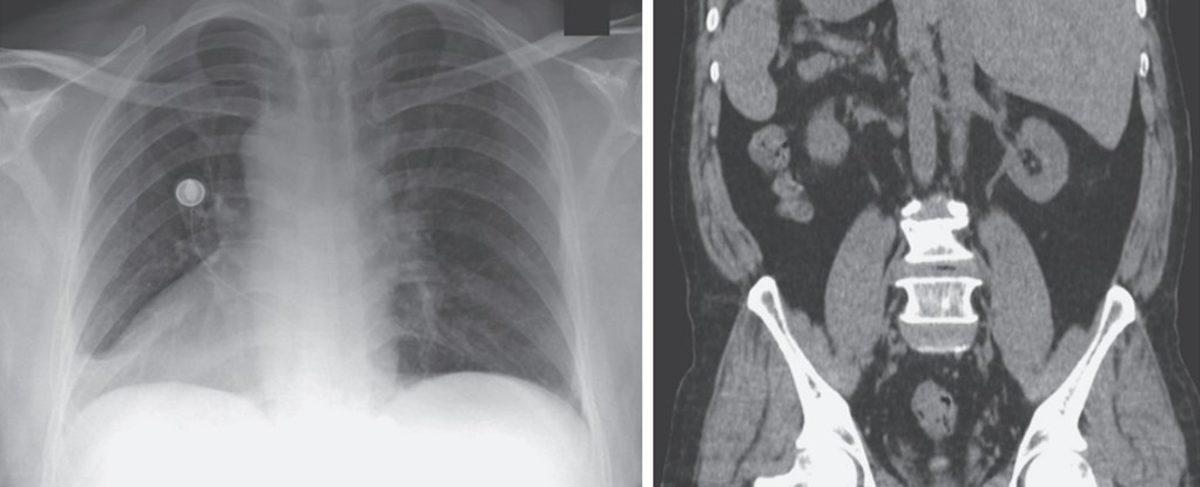

Yapılan incelemelerde, ABD’ye göçmeden önce 20 yıl boyunca sığınmacı kampında yaşayan adamın kalbinin sağda olduğu, diğer organların da ayna simetrisine göre yerleştiği ortaya çıktı. Yani normalde sağda olan karaciğeri solda yer alıyordu.

Adamın hastalığının ise basit bir üst solunum yolu rahatsızlığı olduğu ortaya çıktı. Basit bir ilaç tedavisi uygulanan adam daha sonra taburcu edildi. Situs inversus totalis, organların yerlerinin farklı olduğu vakalar arasında en yaygını ve kabaca her 10 bin kişiden 1’inde görülüyor.